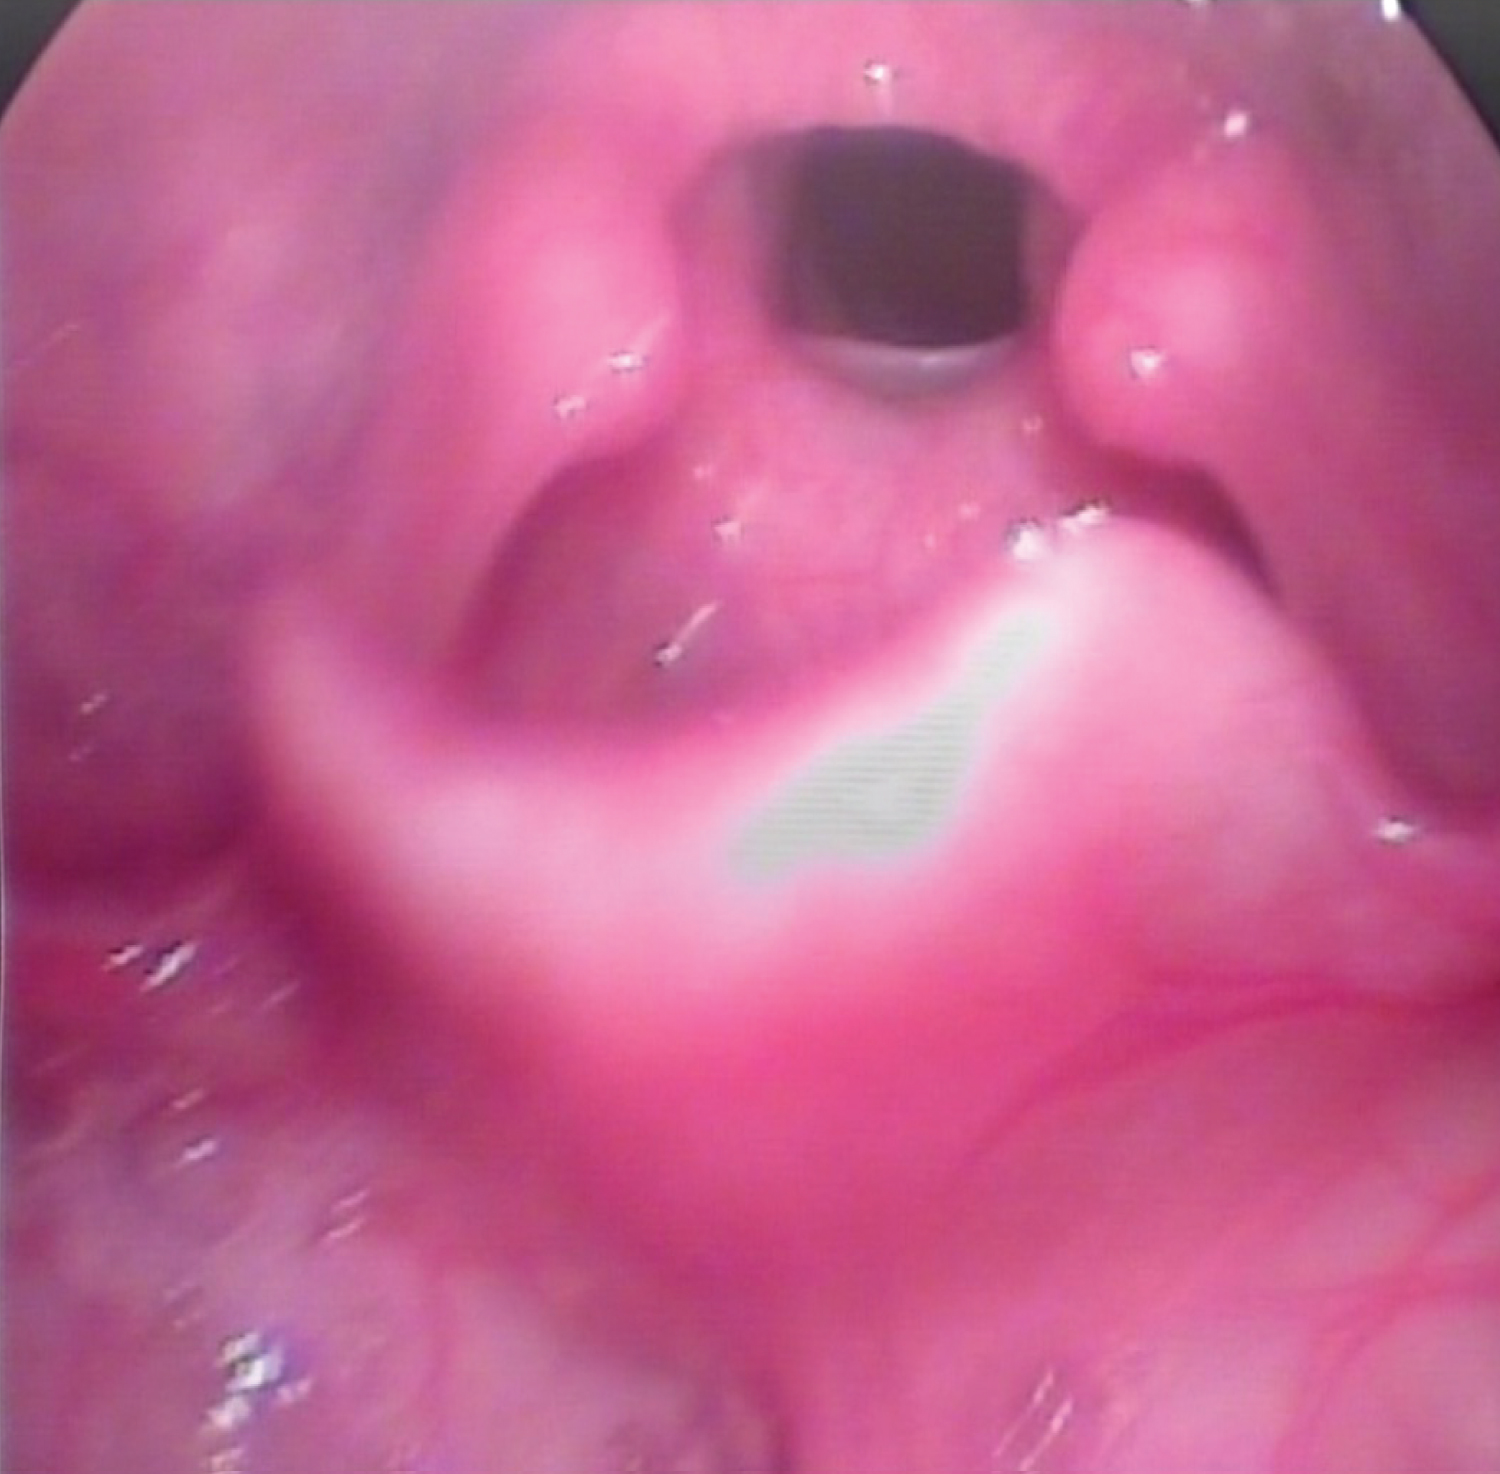

The case was an 11-year-old girl with the Fraser syndrome. Her fingers and toes were joined, which was developed in childhood through the surgery for interfingers folds. Both eyelids were also fused to the face due to the failure to separate the connective tissue during the fetal period. Due to the need for extensive surgical procedures on her eyes, the child was referred to speech therapy for airway examination and status to be evaluated for laryngoscopy of the larynx. Visual evaluation of the larynx was performed using video laryngoscopy, and the acoustic characteristics of voice samples, including vowel sustaining and connected speech, were assessed using Praat software. Auditory-perceptual evaluation of connected speech samples was performed using the GRBAS scale. On this scale, grade of hoarseness, roughness, breathiness, asthenia and strain were assessed on a 4-point Likert scale. On this scale, the severity of the disorder is expressed in each case with a point ranging from 0 to 3, indicating 0 as normal voice and no disturbance and 3 as severe defects in the voice. Auditory-perceptual evaluation was performed by a speech-language pathologist with over 10 years of experience in the evaluation and treatment of voice disorders. Due to the specific circumstances and blindness of the child, the laryngoscopic procedure was performed after several attempts because of poor co-operation. Laryngoscopic findings showed a glottic web extended from anterior to posterior, albeit a cleft was observed in the posterior laryngeal inlet through which the child breathed (Figure 1 and Figure 2).

Figure 1: A photo of the patient's larynx by video laryngoscopy. View Figure 1

Fraser syndrome is one of the rare congenital syndromes characterized by failing the separation of membrane webs, between the parts of the body that must undergo resorption during embryonic development [4]. Since the larynx is one of the parts with membrane fusion, this syndrome may also affect the larynx and especially the vocal folds. This laryngeal disorder can cause for respiration and vocalization. The congenital glottic web is actually a condition in people with this syndrome that causes respiratory and vocalization problems [9,10]. As previously stated, the case reported in this study also had severe problems with vocalization and due to its vocal folds involvement. According to the results of acoustic studies of the voice, her speech had no vocalization in most cases and was similar to whispering. Therefore, this person probably overcomes this problem by using subglottic pressure and noise development in most cases, and has maintained her ability to communicate through speech (Figure 3). However, the voice created in this way has developed a connection with unpleasant and monotonous voice quality. Based on acoustic evaluations, the fundamental frequency of a child's voice sample is greater than the normal range of the fundamental frequency of girls in both vowel sustaining and connected speech [13]. The jitter and shimmer values of the child's voice, which were 1.52 and 15.34, respectively, were much higher than the normal range, indicating a high degree of voice disturbance. The normal range for jitter is less than 0.5 and for shimmer is less than 3 [12,14]. The harmonics-to-noise ratio (HNR), given that its normal value in girls should be above 13, was below this value in both vowel sustaining and connected speech tasks, indicating the absence of normal voice in the individual [15]. The results of auditory-perceptual voice assessment using the GRBAS scale also confirmed the results of acoustic assessments and indicated significant problems with individual voice quality. As shown in Figure 1 and Figure 2, the person was breathing through a cleft in the posterior larynx. Given that other reports of the disease did not specify the acoustic and auditory-perceptual characteristics of the voice for these patients [9,10], the data in this report may be helpful in this regard, and future reports in these patients should be reviewed frequently for the acoustic and auditory-perceptual characteristics of their voice (Figure 3).